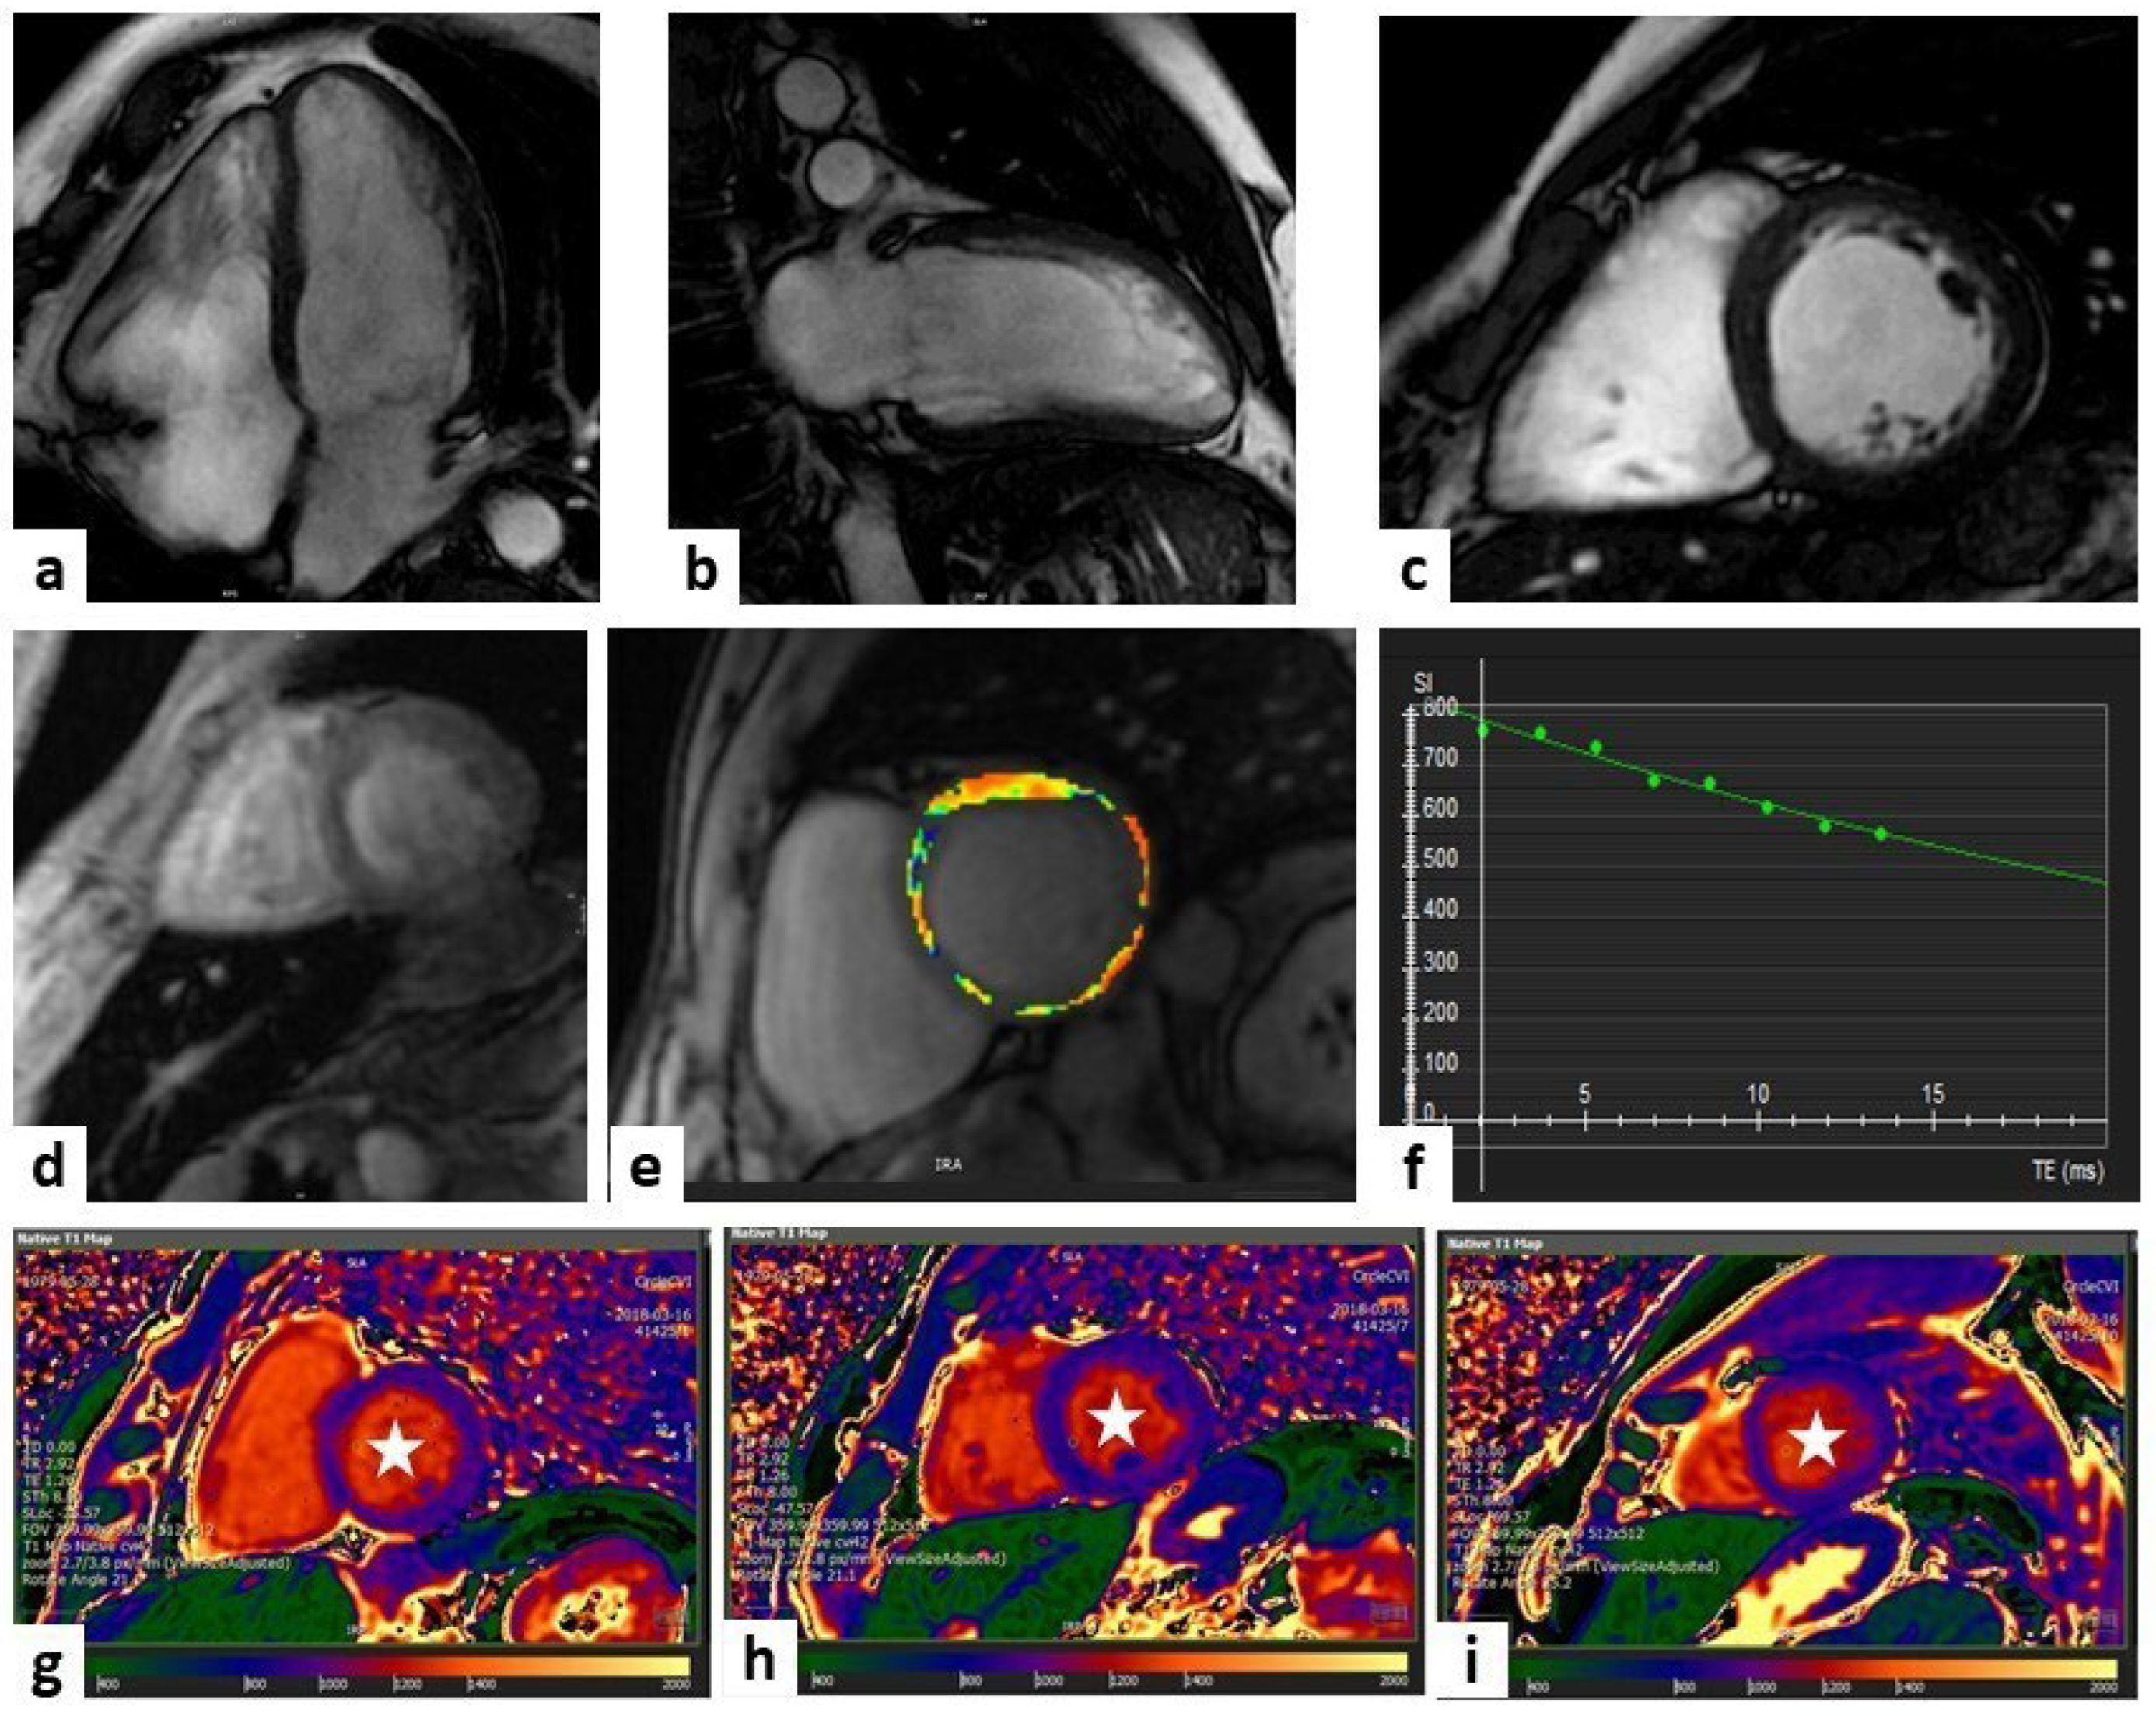

CMR represents the predominant non-invasive imaging modality in the early diagnosis and staging of AFD, as it combines the assessment of cardiac involvement and the characterization of tissue abnormalities [61] (Figure 3).

Figure 3.

Anderson–Fabry disease. One case involves a 67-year-old man who was diagnosed with Anderson–Fabry disease through genetic testing during family screening (because of his affected brother). He remains completely asymptomatic. Cardiac magnetic resonance (CMR) imaging showed concentric LV hypertrophy with a mild reduction in ejection fraction (EF) in steady-state free precession (SSFP) sequences (panels (a–c) show three-chamber, four-chamber, and short-axis views at the basal level, respectively). Panel (d) shows oedema (white arrowheads) at the level of the mid-LV short-axis view (T2-weighted sequence). Panels (e,f) display T1 mapping sequences with a low value in the septum (white arrowheads) and higher values in the lateral wall (white arrowheads with black outlines) at the level of LV papillary muscles and the mid-LV short-axis view, respectively. Panels (g,h) display T2 mapping and extracellular volume (ECV) sequences, respectively, with low values in the septum (white arrowheads) and higher values in the postero-lateral wall (white arrowheads with black outlines) at the level of the mid-LV short-axis view. Late gadolinium enhancement (LGE) sequences display a non-ischemic hyperenhancement pattern (white arrowheads) at the level of the lateral wall (panels (i–l) show three-chamber, four-chamber, mid-LV short-axis, and apical LV views, respectively).

The most common morphological finding is a concentric hypertrophy of LV and of papillary muscles, usually associated with hypertrophy of RV [62,63]. Another typical finding is the presence of LGE, described as myocardial fibrosis areas, in the basal inferolateral mid-wall of the LV with sub-endocardial sparing, found in up to 50% of subjects [58].

Intracellular accumulation of glycosphingolipids causes a reduction in nT1, especially at the basal septum, even at the early stage, that often precedes ventricular hypertrophy and may therefore be useful as a marker for early initiation of enzyme replacement therapy [64]. This makes this method useful for the early identification of cardiac involvement, before the morphological and functional alterations typical of the full-blown phases of the disease [65].

However, it has been shown that, at a more advanced stage of the disease, when inflammation is active and there is a recall of lymphocytes, there is a pseudo-normalization of T1 time that could mislead the clinician [66]. This phenomenon has led experts to propose a three-phase model of AFD: in the initial phase, termed accumulation, there is a reduction in T1 mapping; in the second phase, termed inflammatory, ventricular hypertrophy begins to manifest and T1 mapping can be within a normal range; finally, there is the irreversible terminal phase, with the development of fibrosis and evidence of LGE [66,67].